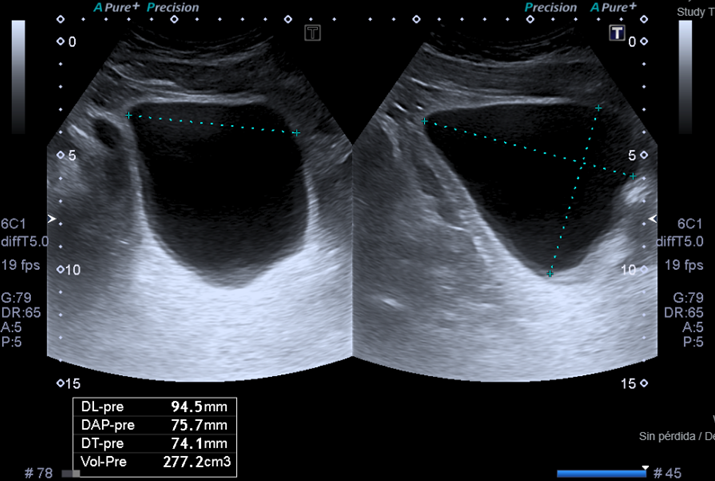

Captura de una ecografía urinaria en la cual se mide el residuo postmiccional

Permite detectar la presencia de un resto o residuo de orina luego de la micción, sugestivo de un vaciado incompleto de la vejiga.